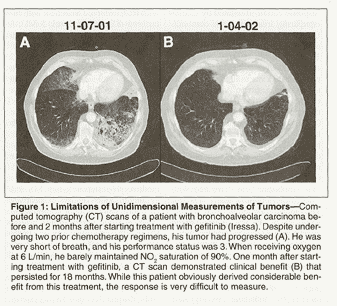

Despite its logical appeal, reduction in tumor burden has proven to be a controversial endpoint. Typically, many recent trials have assessed tumor response using the recently developed Response Evaluation Criteria in Solid Tumors (RECIST). These criteria are derived from a retrospective analysis of measurements obtained from eight clinical trials in which patients were assessed for tumor response.[2] To simplify tumor assessment, RECIST uses unidimensional measurement of the longest diameter of a tumor. Such measurements have reportedly underestimated response to chemotherapy in pleural-based masses, such as malignant pleural mesothelioma,[3,4] tumors with significant surrounding fibrosis, and other tumors, especially in light of current imaging technologies and multimodality approaches.[5] The limitations of this unidimensional approach are illustrated in Figure 1.

In addition, tumor response may underestimate treatment effects on clinical endpoints, including survival, by failing to reflect the magnitude, breadth, and duration of effects on tumor burden.[6] Alternatively, tumor response can overestimate impact on survival if the response is brief or if it does not capture unintended harmful mechanisms of action of the tested treatment. The question of whether ORR correlates with overall survival (OS) and, thus, whether it is an appropriate endpoint is still open to significant debate.